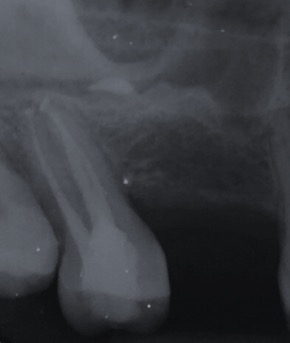

Capita spesso di incontrare denti già devitalizzati in maniera impropria che necessitano, seppur asintomatici, di essere ritrattati per evitare che i granulomi infetti visibili radiograficamente si evolvano riassorbendo tutto l’osso sottostante.